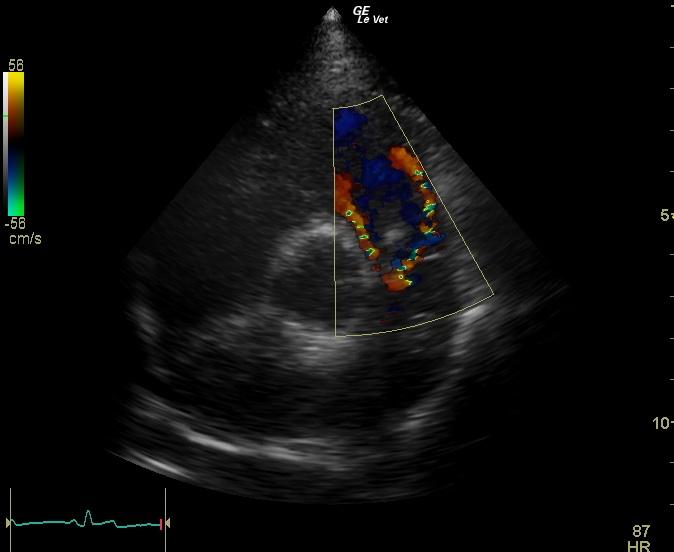

An 11-year-old MN Golden retriever was presented for evaluation due to two episodes of collapse and cyanosis. Additional history was that the patient was more lethargic than usual. Cardiac auscultation did not reveal any abnormalities and blood pressure was normal. Survey radiographs showed a mildly enlarged cardiac silhouette (VHS 11), prominent right ventricle, normal left atrial, and a normal lung pattern.